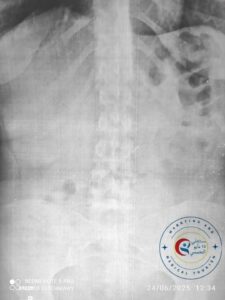

حضرت إلى قسم الطوارئ فتاة تبلغ من العمر 19 عامًا، تعاني من بلع دبوس معدني، وعلى الفور تم إبلاغ فريق مناظير الجهاز الهضمي وبدء الإجراءات اللازمة.

تم حجز الحالة بشكل طارئ، وإجراء منظار معدة عاجل، حيث تم استخراج الدبوس المعدني من جدار المعدة بنجاح.